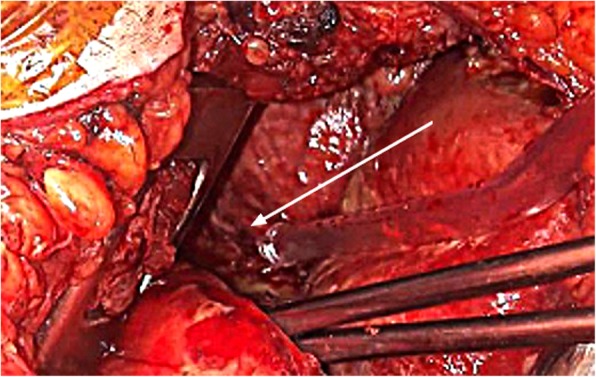

On day 4, cervicotomy and right thoracotomy allowed the evacuation of a right pleural empyema and mediastinal abscesses, and evidenced the presence of a fistula between the mediastinum and right pleural space (Fig. 2). All surgical samples from the mediastinum and the right pleura grew for the same MSSA strain.

Fig. 2.

This picture taken during surgery, evidenced the fistula (white arrow) from the mediastinum to the right pleura